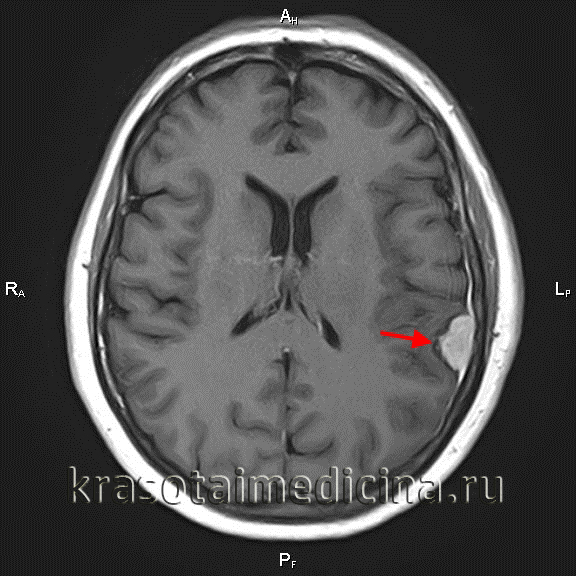

Обязательным в диагностике менингиомы является назначение томографических методов исследования. МРТ головного мозга позволяет определить наличие объемного образования, спаянность опухоли с твердой мозговой оболочкой, помогает визуализировать состояние окружающих тканей. При МРТ в Т1 режиме сигнал от опухоли схож с сигналом от мозга, в режиме Т2 выявляется гиперинтенсивный сигнал, а также отек мозга. МРТ может применяться во время операции для контроля удаления всей опухоли и для того, чтобы получить материал для гистологического исследования. МР спектроскопия применяется для определения химического профиля опухоли.

МРТ головного мозга (С+). Объемное образование в теменной области слева, широким основанием прилежащее к мягкой оболочке

КТ головного мозга позволяет выявить опухоль, но в основном применяется для определения задействования костной ткани и опухолевых кальцинатов. Позитронно-эмиссионная томография (ПЭТ головного мозга) применяется с целью определения рецидивирования менингиомы. Окончательный диагноз выставляется неврологом или нейрохирургом, исходя из результатов гистологического исследования биоптата, которое определяет морфологический тип опухоли.